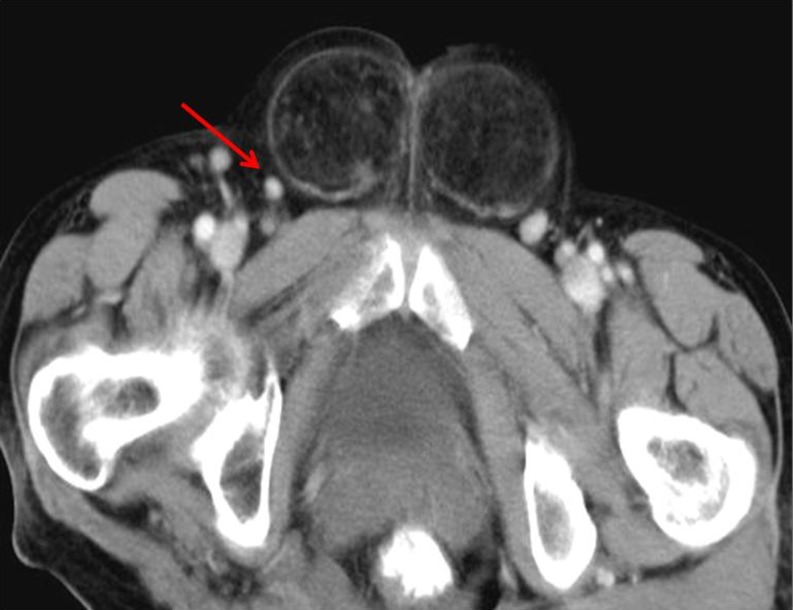

Femoral Hernia

Femoral hernias are more common in women than men, although inguinal hernias are still more common than femoral hernias in women [9]. The femoral canal is the path the femoral artery, vein and nerve leave the abdominal cavity to enter the thigh. Although normally a tight space, sometimes it becomes large enough to allow the abdominal contents into the canal. Hernia is located between the external femoral vein and the gimbernats lacunar ligament medially (Fig. 3).

Fig. 3.

Femoral hernia. CT scan shows contrast filled bowel loops passing through the right femoral canal, medial to the femoral vessels (arrow)